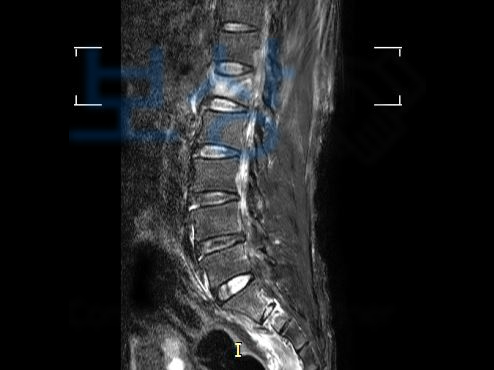

이 사고로 인해 이@@님은

우측 상,하치골가지골절 S32880

우측 천골익 골절 S3210

제 1요추부 3주 골절 S32090

진단을 받으셨고 골절의 모양이 좋지 않아 척추 후방고절술 즉 후방유합술을 받아 안정을 취하셔야 했습니다.